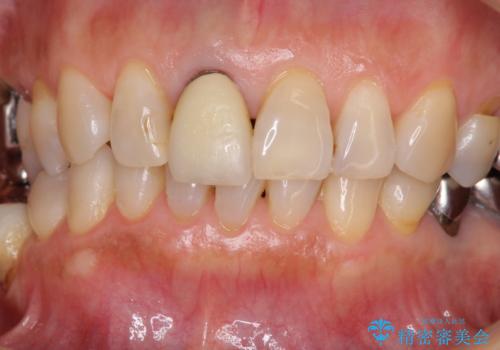

金属を全てセラミックに メタルフリー治療

- 口腔内にある銀歯を全て外したいとのことで来院された患者様です。

土台に含まれている金属も含め、口腔内の金属は全て除去し、抜歯しなければならない歯は抜歯し、オールセラミッククラウンやセラミックインレーにて治療することとしました。

上下奥歯の抜歯を同時期に行わず、下顎の治療を終えてから上顎を抜歯して治療を進めたため、1年ほどの期間を要しました。